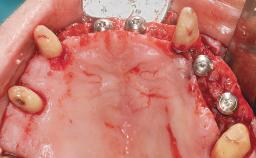

Conventional Loading of Eight Implants in the Maxilla and Final Restoration with a Full-Arch Gold-Ceramic FDP

A 35-year-old Caucasian female presenting with advanced periodontal disease involving both the maxillary and the mandibular dentition was referred for evaluation. The patient, a non-smoker in good general health, requested treatment for recurrent periodontal abscesses, tooth mobility, and discomfort during chewing, as well as restoration of her missing teeth with a fixed prosthesis to improve mastication and esthetics. All residual maxillary teeth exhibited plaque deposits, deep pockets, bleeding on probing, and class III mobility and were evaluated as hopeless. All residual mandibular teeth except tooth 37 could be maintained after periodontal therapy.

Bone Augmentation Horizontal|Staged|Vertical

Augmentation Materials Autogenous block(s)

Bone Volume Deficient vertically or deficient vertically AND horizontally